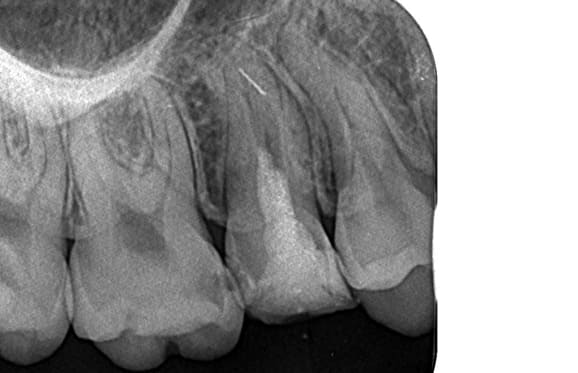

● 先天性の萌出方向異常を部分矯正で治療

藤沢デンタルオフィスの虫歯や破折で先天性の萌出方向異常を部分矯正で治療

01

02

03

04

05

06